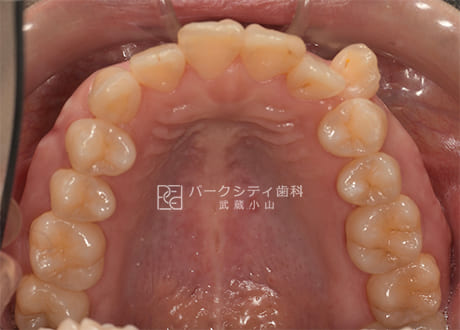

上顎術前

上顎術後